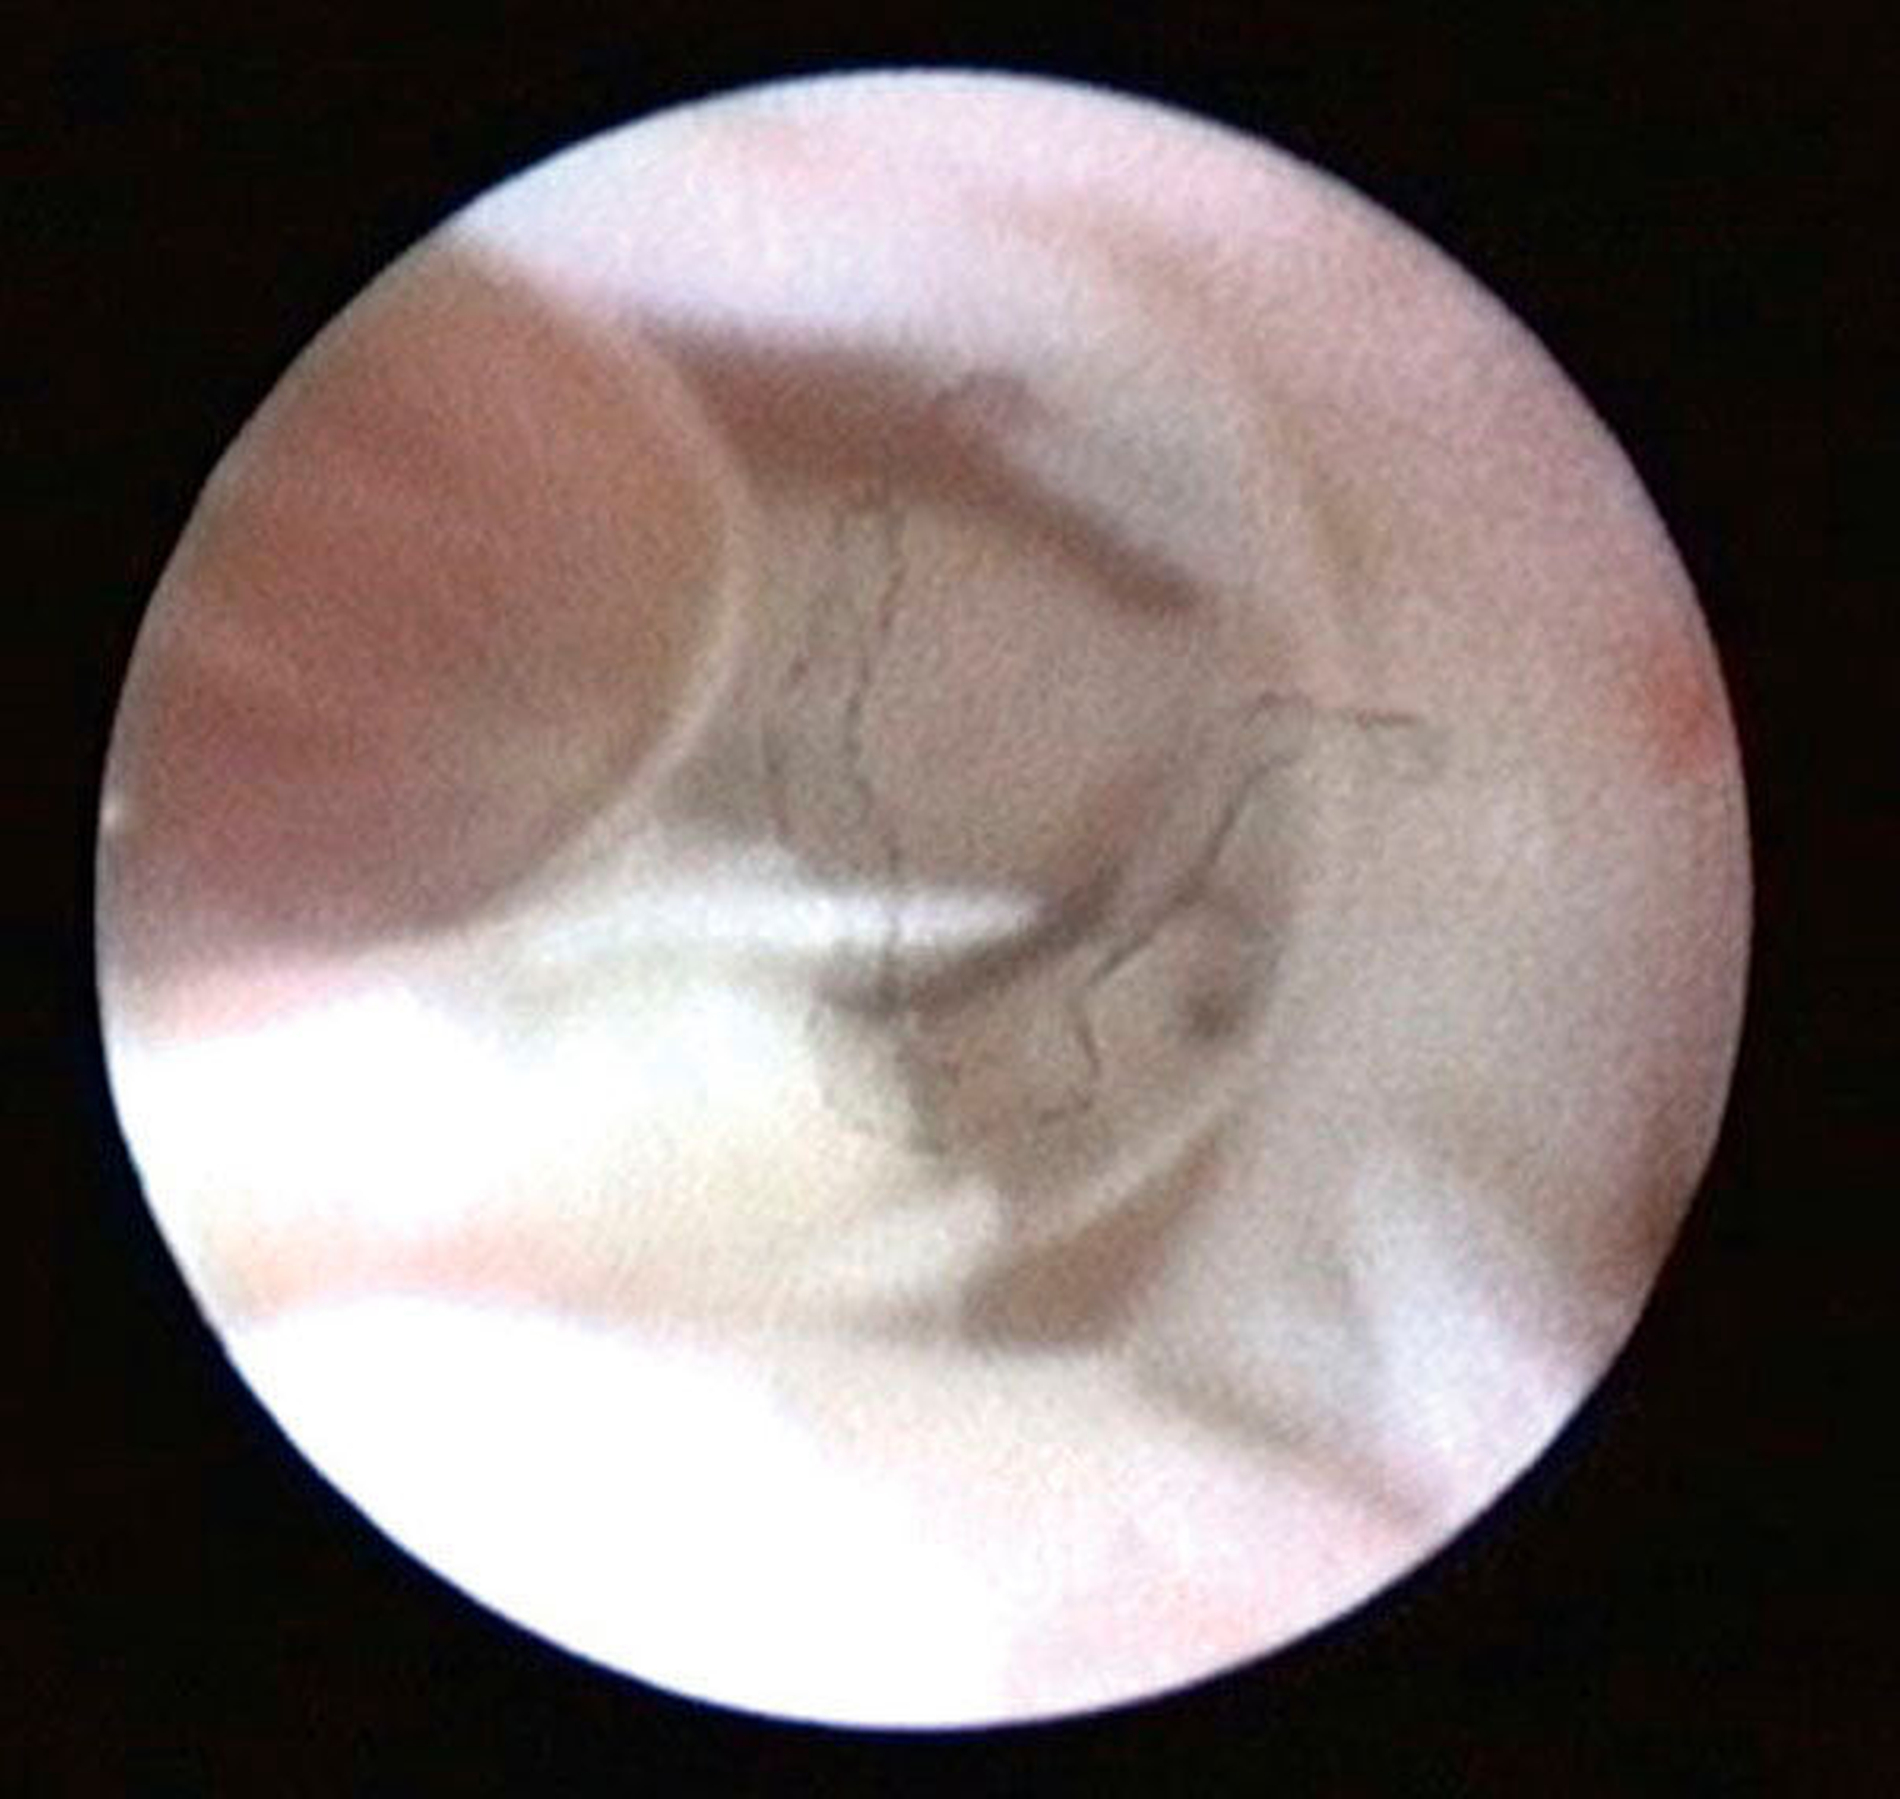

Die Kiefergelenksdestruktion wird als Ergebnis eines katabolen Prozesses verstanden, der die regenerativen Fähigkeiten des Gelenks überlagert und unter anderem durch eine kaskadenartige Aktivierung von Zytokinen vermittelt wird. Dabei kommt es neben einem Verstärkungseffekt durch die Synovial- und Gefäßproliferation zu einer Aktivierung von Osteoblasten. Zytokin-aktivierte Osteoblasten fördern die Rekrutierung und Aktivität von Osteoklasten, diese sezernieren wiederum Enzyme wie beispielsweise Matrix-Metalloproteasen (MMPs), die für den Abbau der extrazellulären Matrix (Hydroxylapatit und Kollagen) des Gelenks verantwortlich sind [Gunson et al., 2011; Zhang et al., 2016; Wang et al., 2012: Ge et al., 2011]. Die Schädigung des Gelenkknorpels wird dabei als „Chondromalazie“ bezeichnet und bei der arthroskopischen Diagnostik je nach Schweregrad im Stadium der Erweichung (Stadium 1), Furchung (Stadium 2), Fibrillation beziehungsweise Fransenbildung (Stadium 3) oder mit subchondraler Knochenexposition (Stadium 4) vorgefunden (Abbildungen 1 bis 3) [Quinn, 1989; Thomas et al., 1991].

Die Kiefergelenksarthroskopie bietet bei gleichzeitiger Lavage eine überragende visuelle Diagnostik des oberen Gelenkraums (Abbildungen 1 bis 7, 13 und 14).